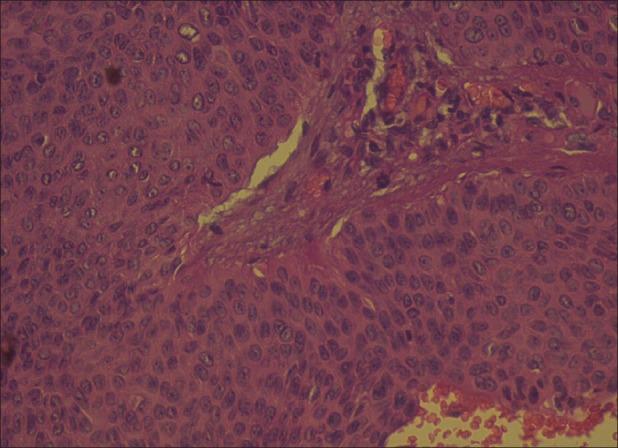

An eccrine poroma is a solitary tumor arising from the eccrine duct epithelium in the epidermis. The lesions commonly occur on the sole of the foot, the hands, and occasionally on the nose, eyelids, neck, and chest. We report a patient who presented with a slow-growing nodular lesion over her left cheek, prompting a diagnosis of basal cell carcinoma or keratoacanthoma. Biopsy from the nodule revealed a well-defined epidermal tumor with uniform small cuboidal cells with rounded deeply basophilic nuclei, few narrow ductal lumina, and occasional cystic spaces confirming the diagnosis of an eccrine poroma.

小汗腺汗孔瘤是一种起源于表皮内小汗腺导管上皮的孤立性肿瘤。病变通常发生在足底、手部,偶尔也出现在鼻子、眼睑、颈部和胸部。我们报告了一名患者,其左脸颊出现一个生长缓慢的结节性病变,最初诊断为基底细胞癌或角化棘皮瘤。对该结节进行活检,发现一个边界清晰的表皮肿瘤,由均匀的小立方形细胞组成,细胞核圆形、深嗜碱性,有少量狭窄的导管腔,偶尔可见囊性间隙,确诊为小汗腺汗孔瘤。